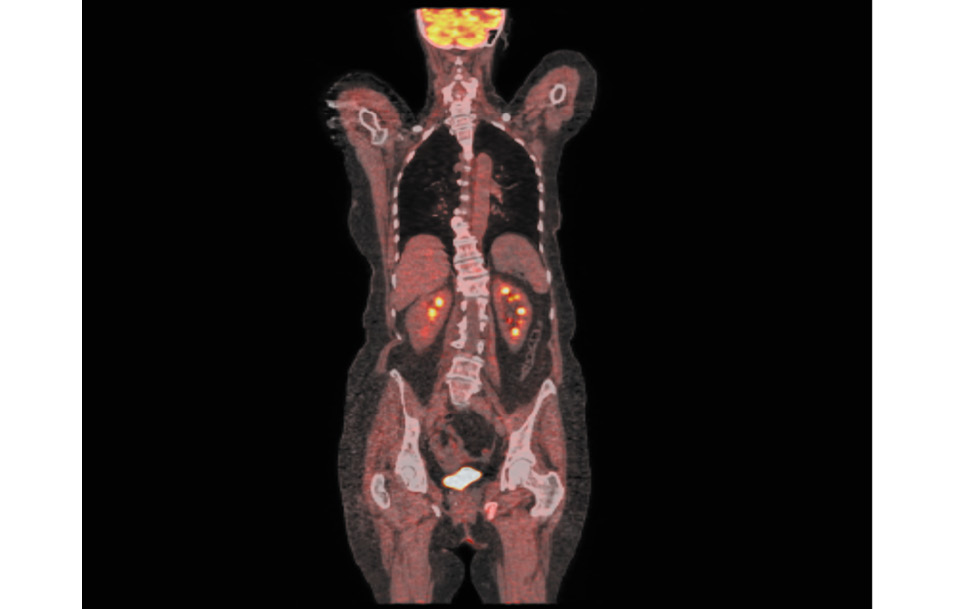

В июне 2019 г. выполнена комбинированная позитронно- эмиссионная и рентгеновская компьютерная томография в режиме всего тела с 18F-фтордезоксиглюкозой – умеренная метаболическая активность фтордезоксиглюкозы в области консолидирующих переломов костей таза слева, что расценено как физиологическое накопление контраста после травмы (рис. 3).

Рис. 3. Результаты комбинированной позитронно-эмиссионной и рентгеновской компьютерной томографии, июнь 2019 г. / Fig. 3. Results of combined positron emission and X-ray computed tomography, June 2019.